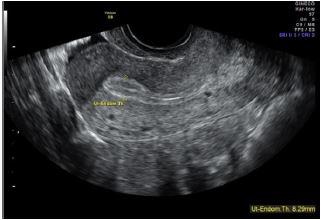

A aparência ultrassonográfica do endométrio durante o ciclo menstrual se correlaciona com as alterações anatômicas e histológicas.

Que fase do ciclo está relacionada com a clássica aparência trilaminar mostrada abaixo?

FONTE: https://brasil.babycenter.com/thread/884235/endom%C3%A9trio-fino?startIndex=30